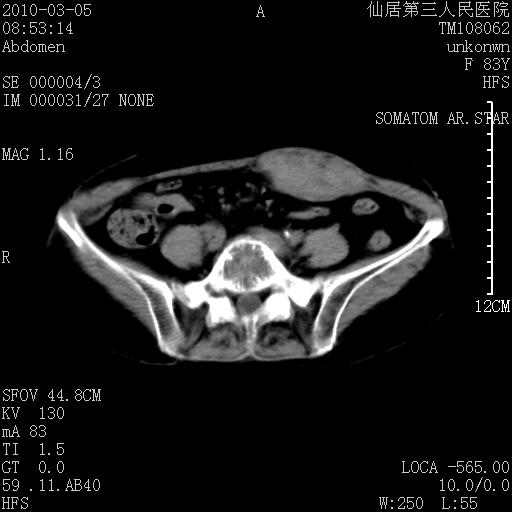

标题: CT24879:腹直肌病变。在线等。

女性,83y,腹痛一周。

考虑:左侧腹直肌神经纤维瘤可能

神经纤维瘤—伴有出血?

有无外伤,血肿或韧带样瘤

考虑左侧腹直肌血肿,肿瘤性病变待排。

增强看看,mfh可能性大,次之可考虑血肿、bfh、转移瘤、神经纤维瘤、侵袭性韧带样纤维瘤等。肝内钙化灶,右肾结石。

支持腹壁纤维肉瘤

血肿,纤维瘤,子宫内膜异位都有可能。